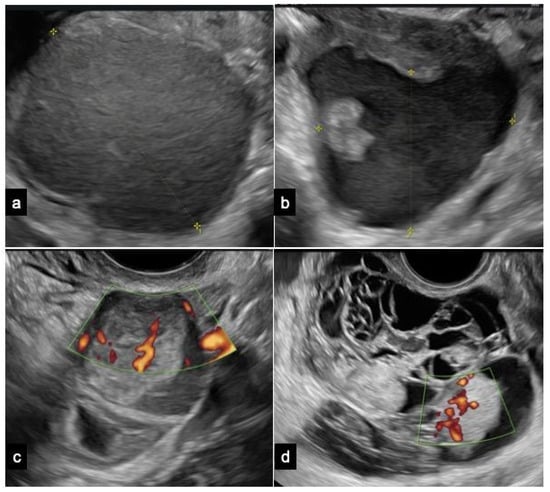

Figure 3.

Flowchart for surgical management of ovarian atypical endometriosis. Abbreviations: MRI, magnetic resonance imaging; HC, hormonal contraceptive; US, ultrasound.